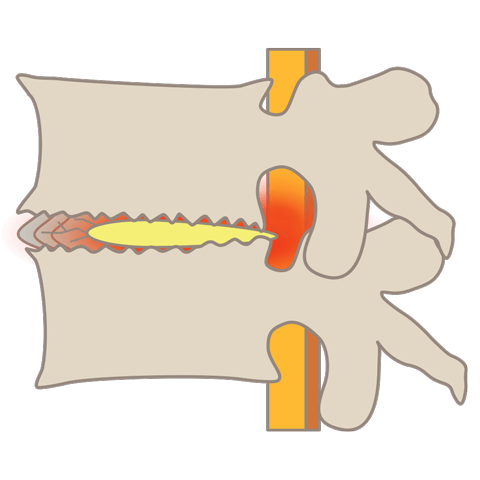

頚椎症は椎間板の変性に加えて骨棘の形成や靭帯の肥厚など複合的な変化によって神経が圧迫される疾患です。

骨棘が形成

椎骨に過剰な負荷がかかり、骨が棘のように突出します。変性が神経を圧迫した場合にはじめて「頚椎症」として症状が現れます。

- 頚椎椎間板ヘルニアは椎間板の髄核が飛び出して神経を圧迫する疾患です。頚椎症は椎間板の変性に加えて骨棘の形成や靭帯の肥厚など複合的な変化によって神経が圧迫される疾患です。両者は併発することが多くあります。頚椎椎間板ヘルニアについてはこちら。